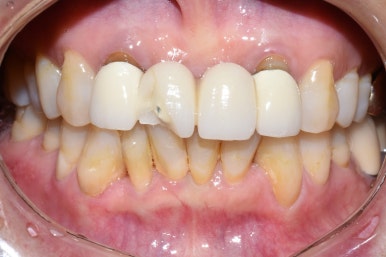

이번에는 저희 치과를 찾아오신 외국인 환자분의 앞니 브릿지 치료 사례를 한번 보겠습니다.

[환자분의 동의를 얻은 사진만 게시합니다]

방금 넘어져서 앞니가 깨졌다며

잘하는 치과 수소문해서 소개받고 오신 외국인환자분입니다.

앞니깨짐

처음에는 크라운을 하면 될거라 예상했지만

자세히 보니 앞니가 뿌리 부분까지 쪼개져서 벌어져 있었습니다.

이렇게 전 후 사진비교해보니

브릿지를 하고 훨씬 나아졌습니다.

환자분께서 나머지 다른 앞니들은 충치도 있고 예뻐지려고 라미네이트를 할 예정이라고 하셨기 때문에

조금더 본인 치아색보다 하얀 색으로 진행하였습니다.